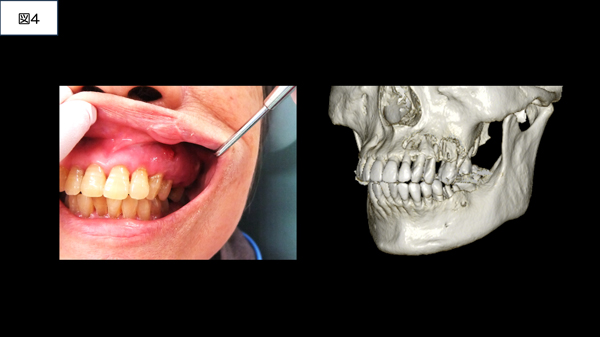

口腔は他の臓器と異なり、セルフチェックが可能な臓器です。定期的に口の中をセルフチェックすれば、口腔がんは発見でき、早期治療につながります。口腔がんのできやすい場所は舌・歯肉・頬の粘膜です(図3)。中高年齢の方は、毎月1回のセルフチェックを強くお勧めします(図4)。セルフチェックの仕方については、日本口腔外科学会に詳細がありますのでご参照ください(https://www.jsoms.or.jp/public/soudan/selfcheck/)。口腔がんの原因は主にタバコとお酒です。他にも不潔な口腔衛生状態、合っていない入れ歯や歯の尖による慢性刺激、ウイルス)感染なども原因とされています。特に、タバコやお酒等の習慣がある方は、怪しいと思ったら直ぐに、かかりつけ歯科医に相談して下さい。